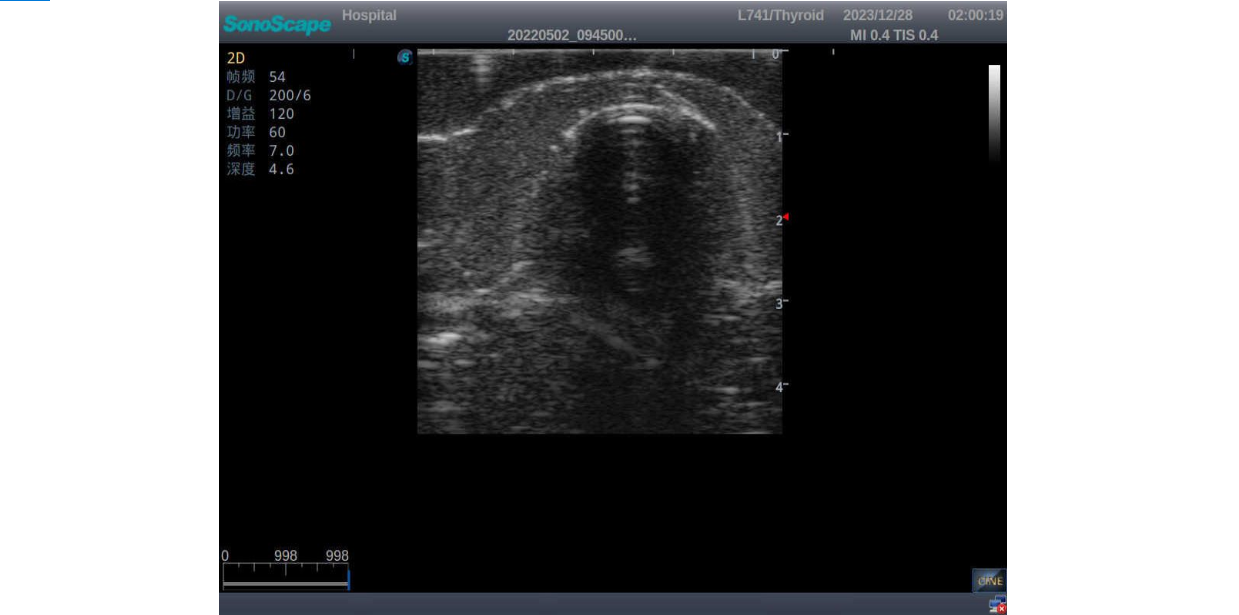

3) It comes with four (4) thyroid modules and can show five (5) ultrasonic images: normal thyroid, thyroid adenoma, thyroid cancer, nodular goiter, thyroid cyst

Thyroid adenoma with well-defined border and smooth uniform halo

Thyroid cancer with irregular mass, unclear border, uneven internal echo or calcification strong echoes

Nodular goiter with irregular border and varying sizes of low echo, isoechoic, or high echo nodules